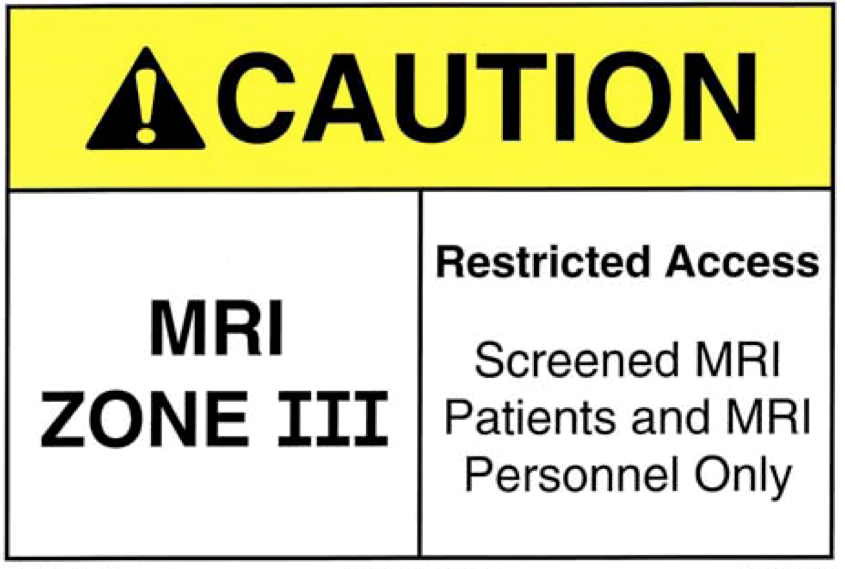

MRI Zone 3

Zone 3: Control Room

All metal removed

Locks on doors

Caution signs

Authorised access only